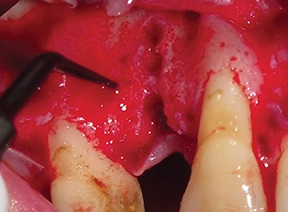

The recipient site was then prepared by perforating the cortical plate with a piezoelectric insert (ES012T) to expose the marrow spaces and promote vascular ingrowth (Fig. 14).

Fig. 14: Recipient site prepared by perforating the cortical plate